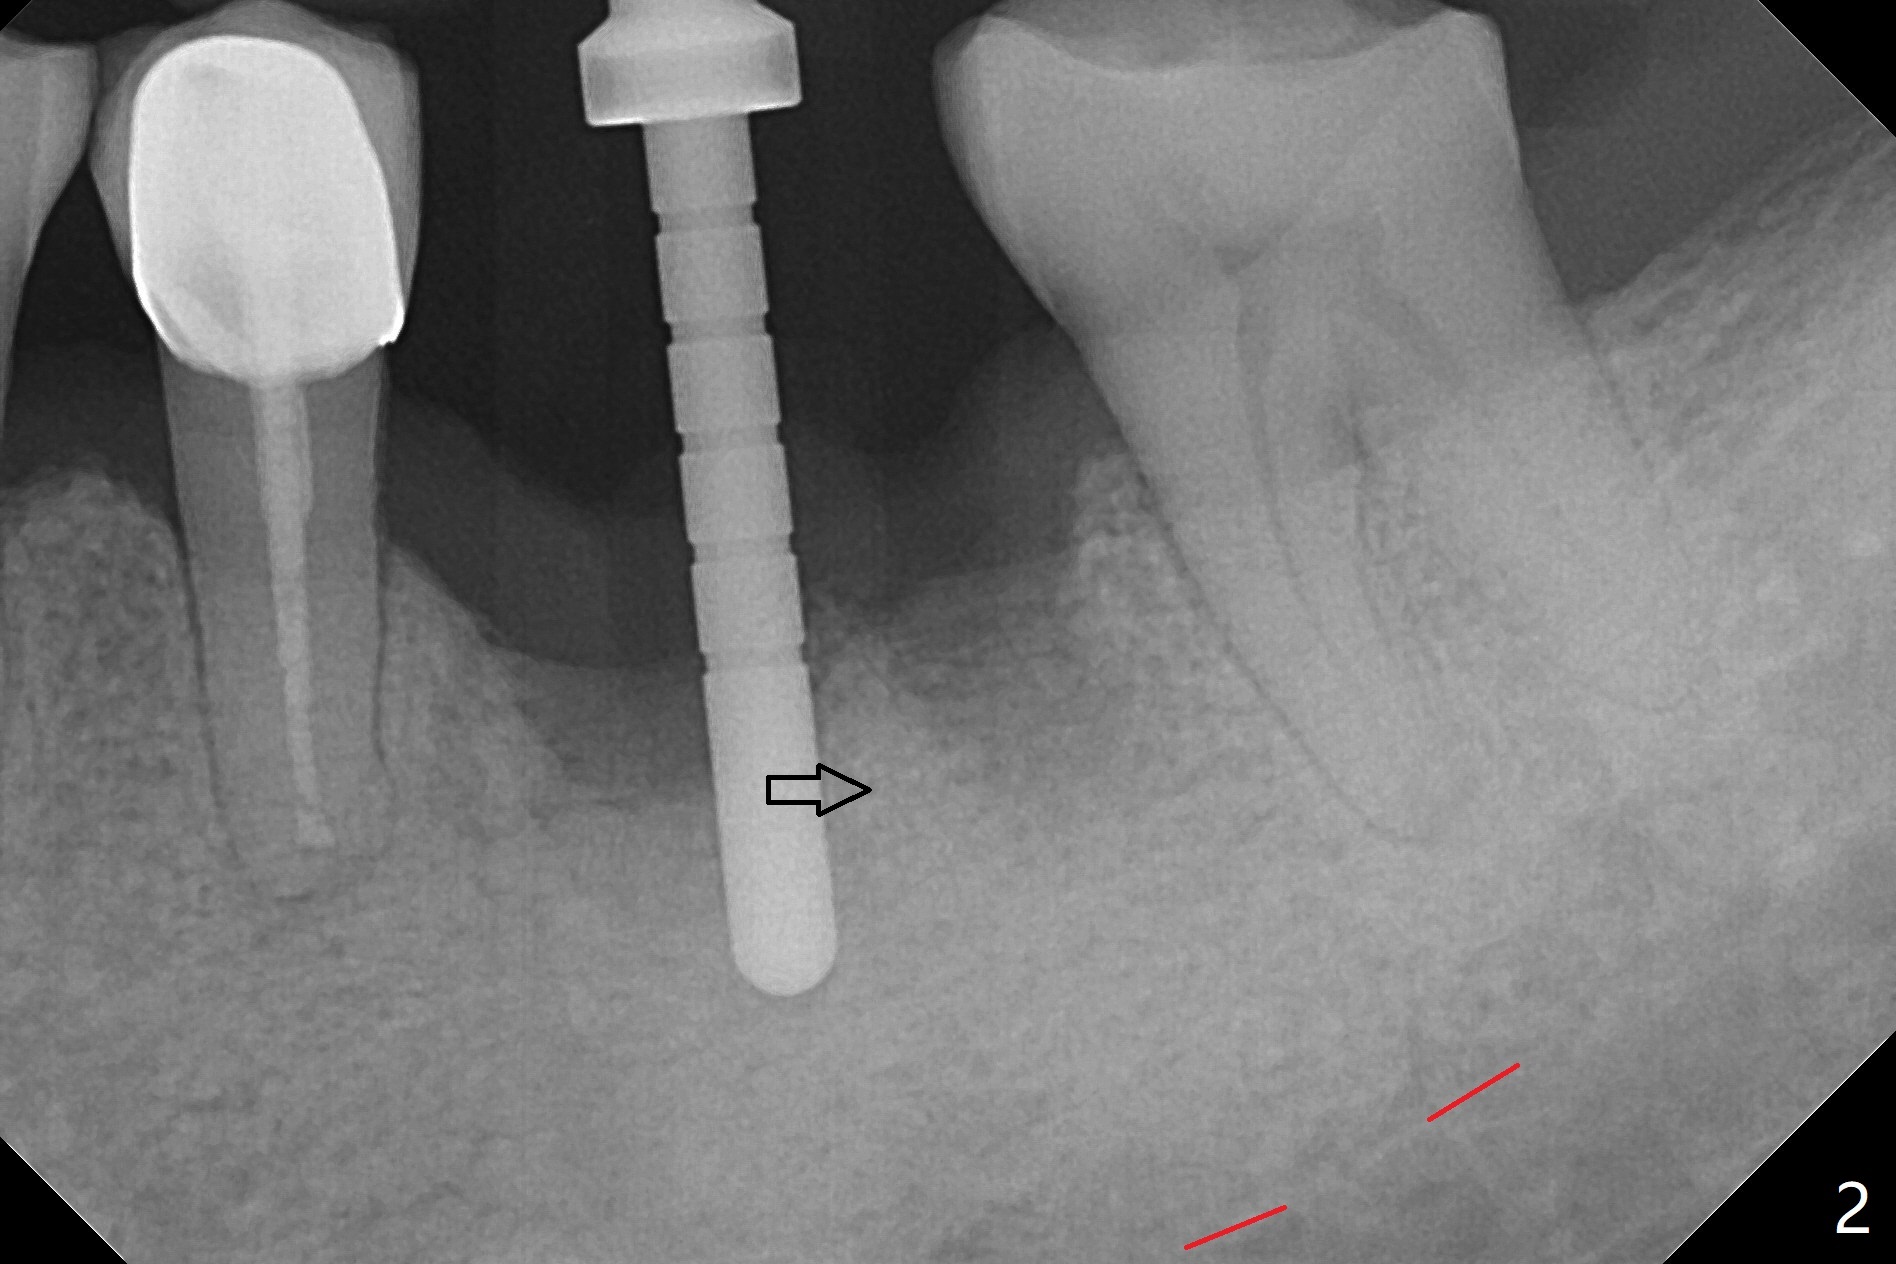

After extraction of the tooth #19 with mesial root fracture (Fig.1 ^) and curettage, the initial osteotomy in the septum is found to need to be distalized (Fig.2 arrow). Following sequential osteotomy, a 5x17 mm tap cannot reach the expected depth (Fig.3 yellow dashed line) because of the dense bone. A shorter implant is placed with >60 Ncm (Fig.4). An immediate provisional is fabricated after placement of a 4.5x5 mm abutment and Vanilla/Osteogen graft (Fig.5 *). The mesial and distal sockets heal 4 months postop (Fig.6). The bone density in the mesial and distal sockets continues to increase when a crown is cemented (~4.5 months postop, Fig.7). The implant at #19 was placed in the middle of the bone (Fig.8).